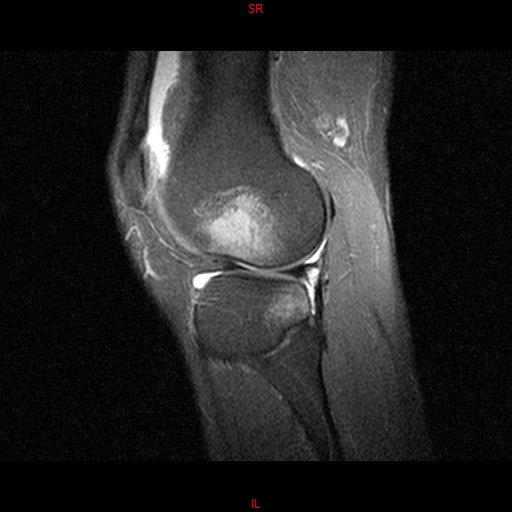

• RESONANCIA PATOLÓGICA MENISCOPATIA INTERNA DP SAGITAL